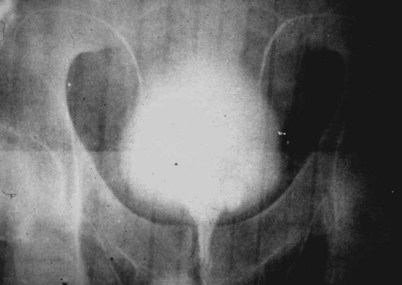

If a large amount of fluid is found in the vasal lumen and microscopic examination reveals the presence of sperm, the obstruction is toward the seminal vesicle end of the vas. In these cases the vas is usually markedly dilated. A 2-0 Proline suture can be passed toward the seminal vesicle end of the vas and a clamp placed on the Proline when the suture passes no farther. This is particularly useful for delineating the site of inguinal obstruction from prior groin surgery. If the obstruction is proximal to the inguinal scar, formal vasography is performed by passing a No. 3 whistle-tip ureteral catheter toward the seminal vesicle end of the vas. A 16-Fr Foley catheter is placed in the bladder, and the balloon is filled with 5 mL of air. Placing the balloon on gentle traction before vasography prevents reflux of contrast into the bladder, which can obscure detail (Fig. 22–5). The air-filled balloon also identifies the location of the bladder neck relative to any obstruction. After the vasa have been cannulated, vasograms are performed with the injection of 0.5 mL of water-soluble contrast media (Fig. 22–6). If vasography reveals obstruction at the site of the ejaculatory ducts (Fig. 22–7), indigo carmine is injected in both vasa to assist a transurethral resection (TUR) of the ejaculatory ducts (see Diagnosis later). If both vasa are visualized after injection of contrast into only one vas (Fig. 22–8), it means both vasa empty into a single cavity, usually a midline ejaculatory duct cyst.

Figure 22–5 Placing the balloon on gentle traction before vasography prevents reflux of contrast into the bladder, which can obscure detail.